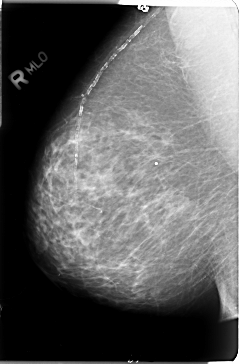

B_3027_1.RIGHT_MLO

LEFT_MLO LINES 4696 PIXELS_PER_LINE 3184 BITS_PER_PIXEL 12 RESOLUTION 50 OVERLAY

RIGHT_MLO LINES 4720 PIXELS_PER_LINE 3120 BITS_PER_PIXEL 12 RESOLUTION 50 NON_OVERLAY

FILE: B_3027_1.LEFT_MLO.OVERLAY

TOTAL_ABNORMALITIES 2

ABNORMALITY 1

LESION_TYPE MASS SHAPE IRREGULAR MARGINS ILL_DEFINED

ASSESSMENT 4

SUBTLETY 4

PATHOLOGY MALIGNANT

TOTAL_OUTLINES 1

BOUNDARY

ABNORMALITY 2

LESION_TYPE CALCIFICATION TYPE PLEOMORPHIC DISTRIBUTION CLUSTERED